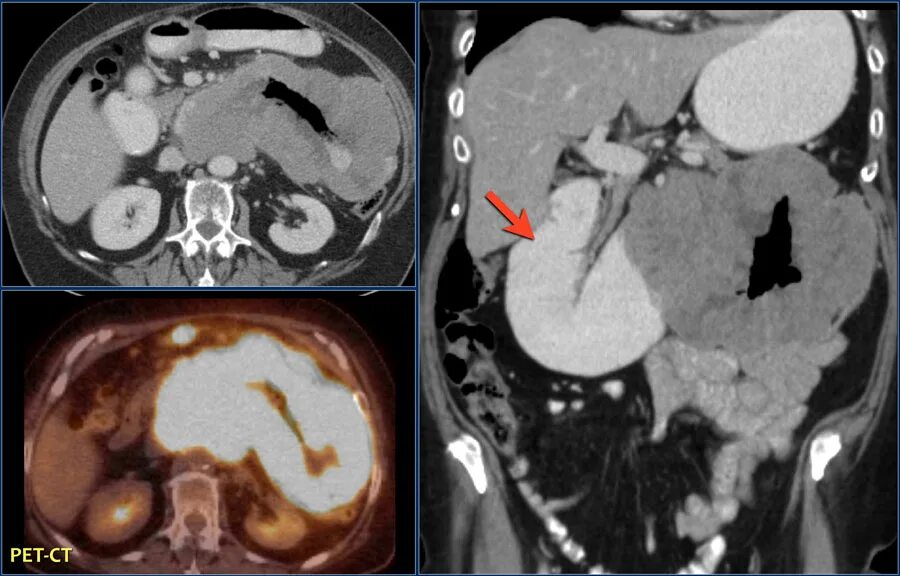

Лучевая диагностика опухолей поджелудочной железы. Методы диагностики патологии поджелудочной железы. Методы исследования поджелудочной железы. Метод исследования поджелудочной железы.

Лучевая диагностика опухолей поджелудочной железы. Методы диагностики патологии поджелудочной железы. Методы исследования поджелудочной железы. Метод исследования поджелудочной железы. Опухоль головного мозга стадии. Опухоль головного мозга симптомы. Проявление опухоли головного мозга. Степени опухолей головного мозга.

Виды роста злокачественных опухолей. Рост злокачественных новообразований. Злокачественные опухоли характеризуются. Форма злокачественной опухоли. ПЭТ кт онкология глиома. Метастазы в печени на ПЭТ кт.

ПЭТ кт онкология глиома. Метастазы в печени на ПЭТ кт. Лимфангиома брыжейки кт. Лимфома брыжейки тонкой кишки кт.